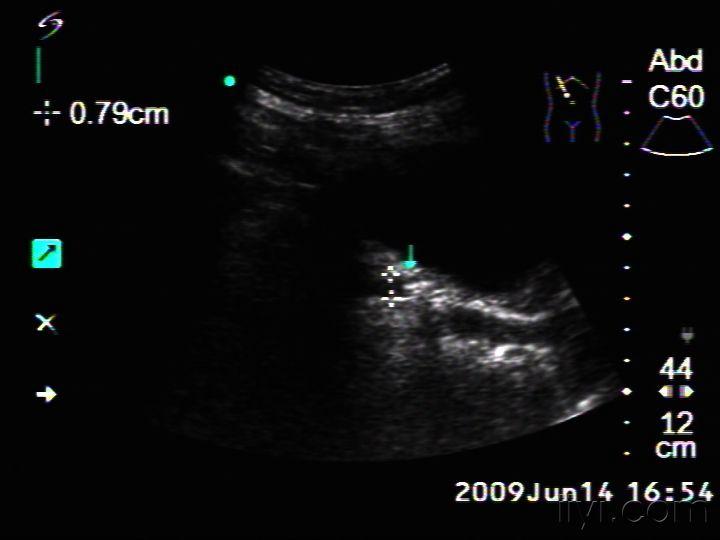

今天做的一例输尿管末端结石 超声医学讨论版 爱爱医医学论坛

临床必备肾结石输尿管结石超声表现一览

寻找输尿管结石的个人经验和方法 超声医学讨论版 爱爱医医学论坛